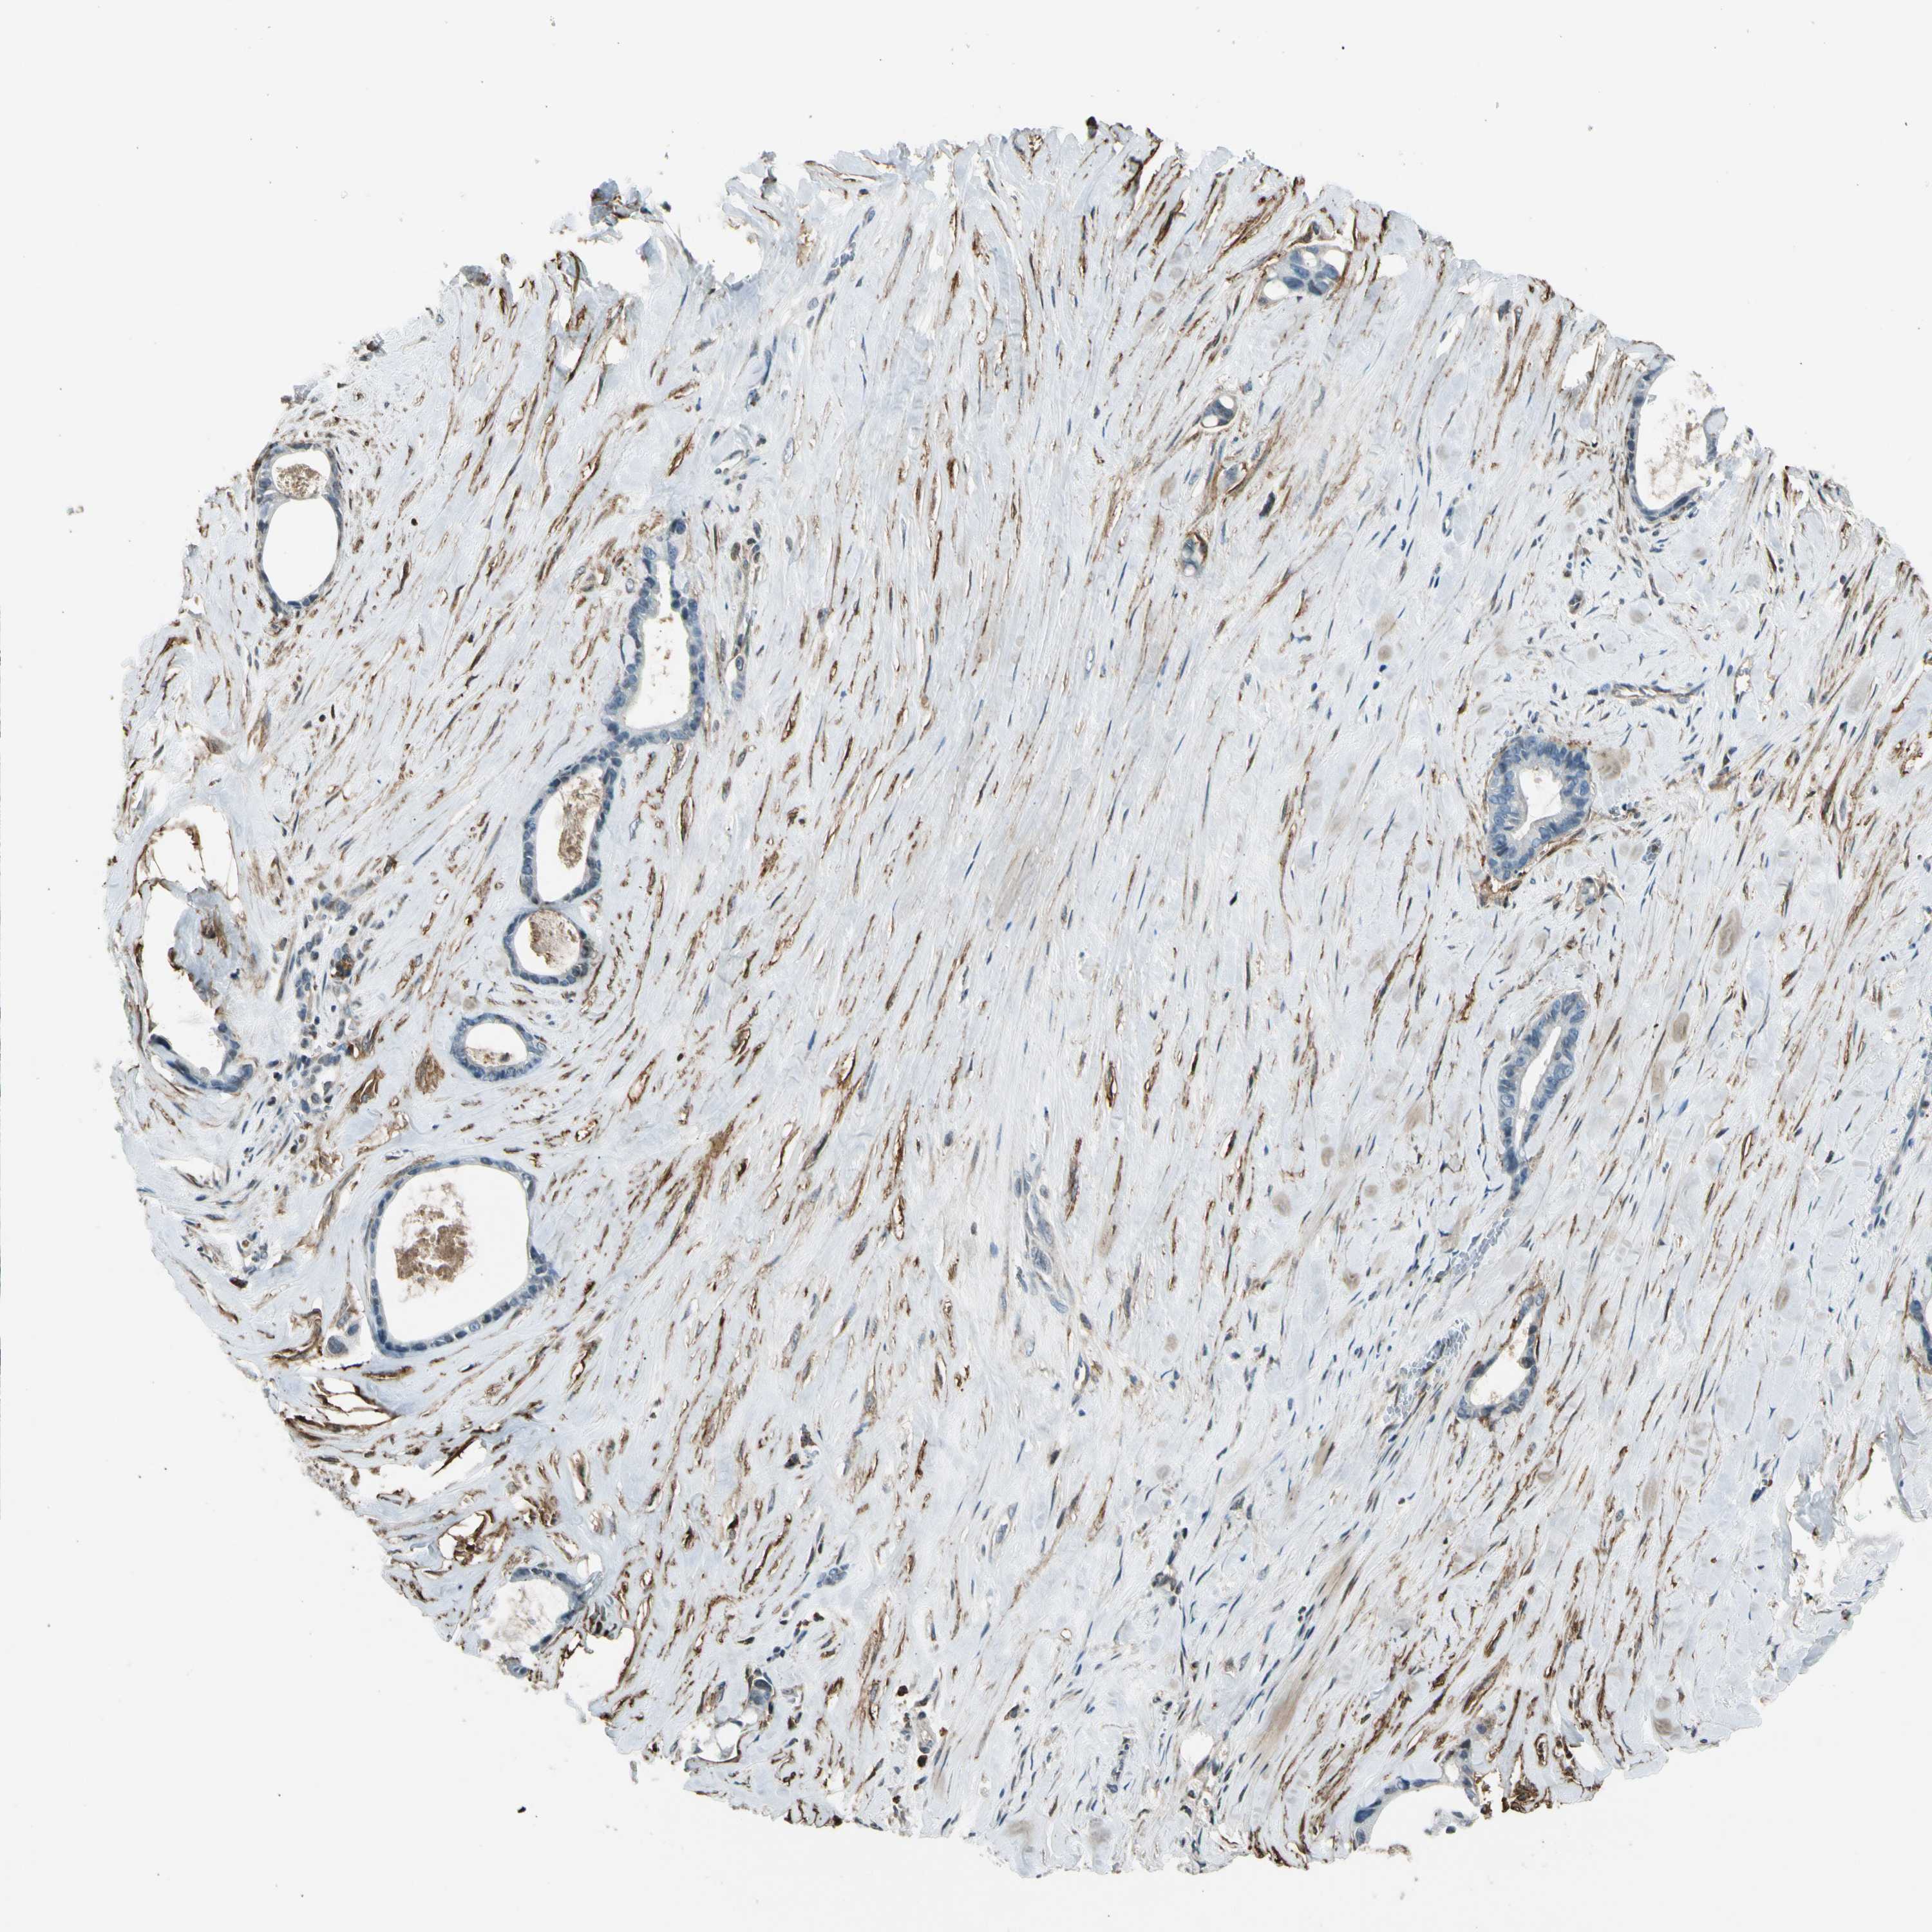

LIVER CANCER - Protein expressioni

A mouse-over function shows sample information and annotation data. Click on an image to view it in a full screen mode. Samples can be filtered based on level of antibody staining by selecting one or several of the following categories: high, medium, low and not detected. The assay and annotation is described here.

Note that samples used for immunohistochemistry by the Human Protein Atlas do not correspond to samples in the TCGA dataset.

Antibody stainingi

Antibody staining in the annotated cell types in the current human tissue is reported as not detected, low, medium, or high, based on conventional immunohistochemistry profiling in selected tissues. This score is based on the combination of the staining intensity and fraction of stained cells.

Each image is clickable and will lead to virtual microscopy that enables deeper exploration of all samples and also displays staining intensity scores, fraction scores and subcellular localization as well as patient and tissue information for each sample.

Antibody HPA007534

Antibody CAB008376

Staining

High

Medium

Low

Not detected

Intensity

Strong

Moderate

Weak

Negative

Quantity

>75%

75%-25%

<25%

None

Location

Nuclear

Cytoplasmic/membranous

Cytoplasmic/membranous,nuclear

Cholangiocarcinoma

Carcinoma, Hepatocellular, NOS